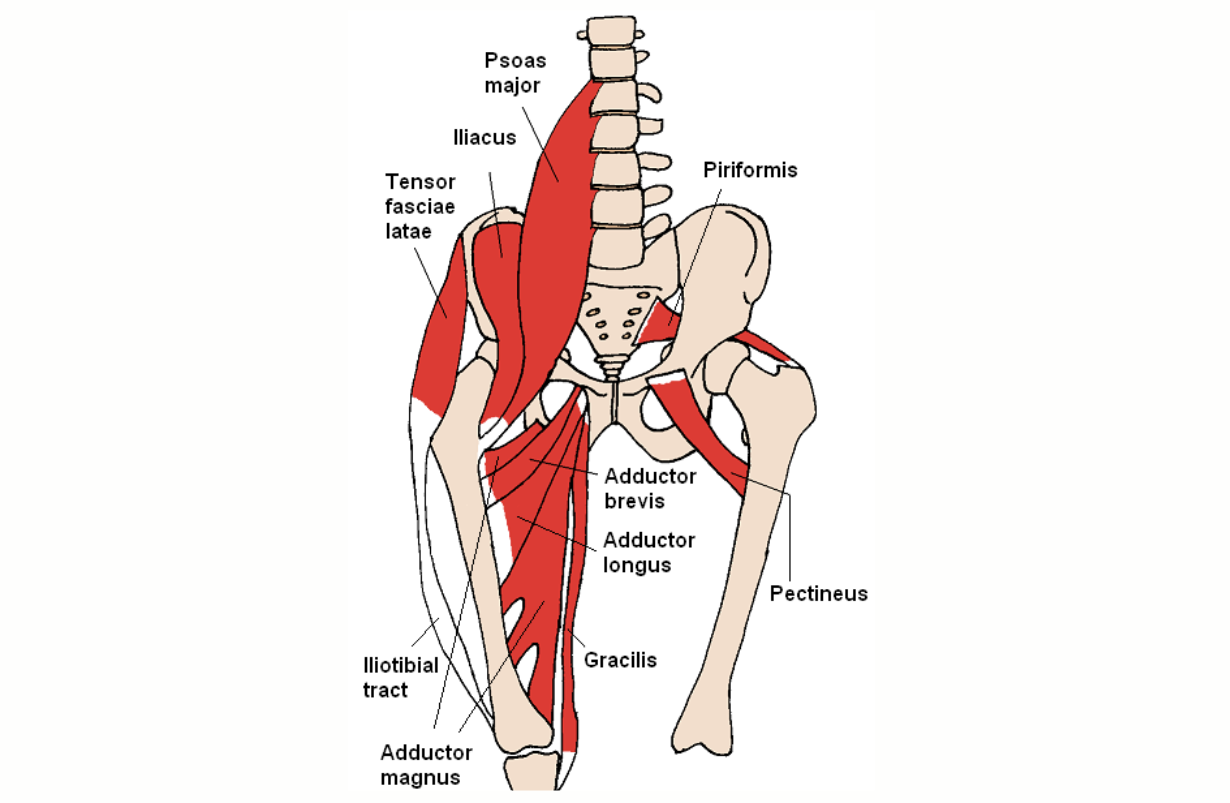

Torn Adductor

Partial or complete rupture of the adductor brevis, longus and/or magnus muscles, the muscles that draw the legs together. BENEFICIAL POSES: Jathara Parivartanasana, Ardha Chandrasana, Utthita Hasta Padangustasana,. EXPLANATION: The anterior third of the gluteus medius and minimus actually adduct and internally rotate the leg, easing stress on the adductors, and promoting their healing. REFERENCES: Kelley K, Slattery K, Apollo K. An electromyographic analysis of selected asana in experienced yogic practitioners. Mov Ther. 2018 Jan;22(1):152-158. doi: 10.1016/j.jbmt.2017.05.018. Epub 2017 May 31. Beazley D, Patel S, Davis B, Vinson S, Bolgla L.Trunk and hip muscle activation during yoga poses: Implications for physical therapy practice. Complement Ther Clin Pract. 2017 Nov;29:130-135. doi: 10.1016/j.ctcp.2017.09.009. Epub 2017 Sep 14.